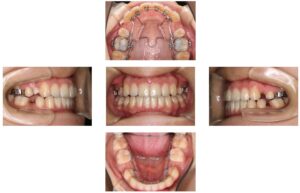

| 治療内容 | フルリンガルブラケット |

| 上顎左右4、下顎左右5抜歯 | |

| 治療期間 | 2年10か月 |